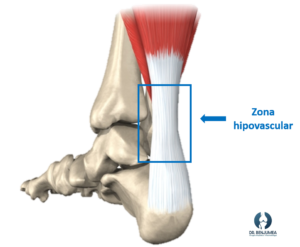

Realmente cuando existe una rotura aparecen dos causas de forma habitual, una tensión excesiva que debe soportar el tendón y una degeneración previa en la zona afectada. Esta zona suele coincidir con una región hipovascular (zona con poco aporte sanguineo) que predispone a la lesión. La zona degenerada es más débil que el resto del tendón, por lo que, en esos momentos de estrés, sobre todo si son repetitivos, el tejido va debilitándose hasta que finalmente acaba por romperse.